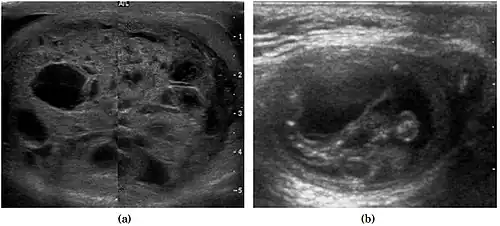

-

Fig. 29. Undescended testis. (a) Normal testis in the scrotum. (b) Atrophic and decreased echogenicity of the contralateral testis of the same patient seen in the inguinal region.